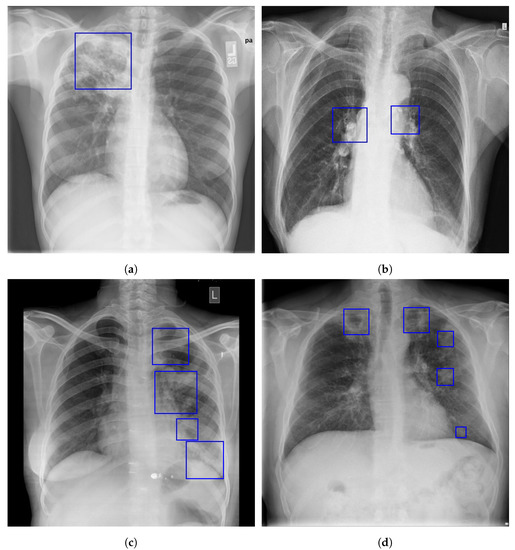

Figure 1.

Examples of primary and post-primary PTB manifestation in a CXR []. The following are indicated by the blue boxes: (a) coalescing air space opacity on the right upper lobe; (b) enlarged hilar and mediastinal lymph nodes; (c) a thick-walled cavitary lesion in the left upper lobe; (d) bilateral apical thick-walled cavities and multifocal satellite air space opacities.

In primary pulmonary tuberculosis, the first areas of infection can be anywhere in the lung and can have any number of non-specific appearances, from patches of consolidation to spots that are too small to be seen. Only 10 to 30% of early TB infections show cavitation, and 70% of children and 90% of adults have radiographic signs of parenchymal infection []. The majority of the time, the infection becomes a localized, caseating granuloma (also known as a tuberculoma), and it typically calcifies, becoming a Ghon lesion. The more notable feature is the often right-sided, ipsilateral hilar and contiguous mediastinal (paratracheal) lymphadenopathy, which is particularly common in pediatric cases, Figure 1a,b. Pleural effusions are more frequent in adults, seen in 30–40% of cases, whereas they are only present in 5–10% of pediatric cases []. As the host mounts an appropriate immune response, both the pulmonary and nodal disease resolve. When a calcified node and a Ghon lesion are present, the combination is known as a Ranke complex [,].

Post-primary infections have a strong propensity for the upper zones. In most cases, the upper lobes’ posterior or lower lobes’ superior segments are where post-primary TB in the lungs typically manifests itself. Patchy consolidation or poorly defined linear and nodular opacities are the usual symptoms of post-primary tuberculosis, and examples are given in Figure 1c,d. Primary infections have a far lower chance of cavitating than post-primary infections. Endobronchial spread along nearby airways is a relatively common finding, resulting in well-defined 2–4 mm nodules. Only about a third of cases have hilar nodal enlargement. Although they are less frequent, lobar consolidation, tuberculoma development, and miliary TB are the other recognized features of post-primary TB. Only 5% of cases of post-primary TB are caused by tuberculomas, which present as a well-defined, spherical mass that is usually found in the upper lobes. They can be up to 4 cm in size and are often solitary. Most frequently, little satellite lesions are observed. Superimposed cavitation may develop in 20–30% of instances [,].